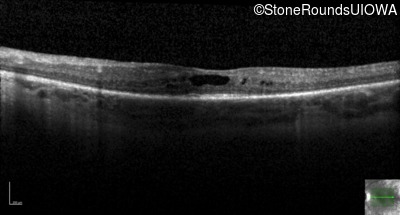

Optical Coherence Tomography - Right - 20/60 -1

Exemplar / OCT Stack